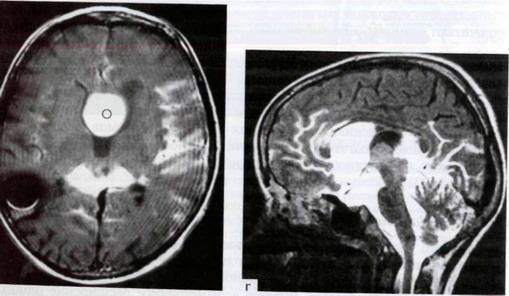

Рис. 38-4. Супраселлярная арахноидальная киста, расщепившая прозрачную перегородку

Рис. 38-4. Супраселлярная арахноидальная киста, расщепившая прозрачную перегородку и внедрившаяся в левый боковой желудочек: